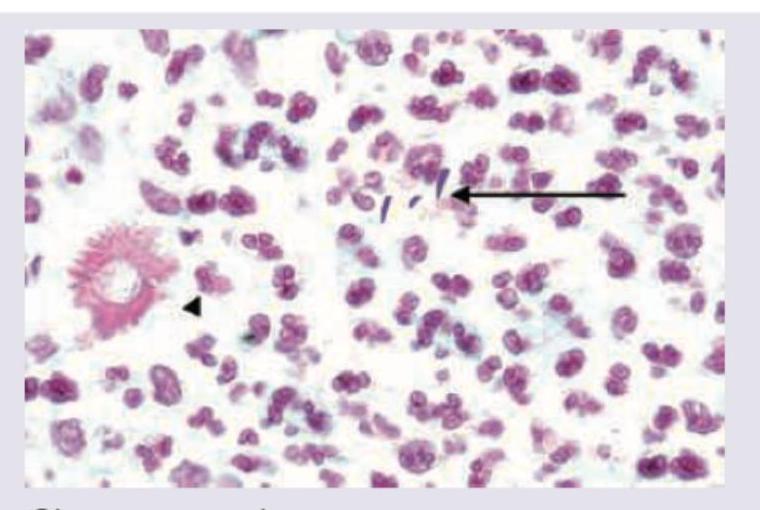

A carpenter presents with a nodule on dorsum of hand which ulcerates after few days and has not healed for last 2 months. Biopsy of lesion was performed and shown below. All are used in management of this condition except:

Explanation: ***Cotrimoxazole*** - Cotrimoxazole (trimethoprim-sulfamethoxazole) is an **antibiotic** and is **not indicated** for the treatment of **sporotrichosis**, which is a fungal infection. - The image shows budding yeasts and cigar-shaped forms typical of **Sporothrix schenckii**, alongside a giant cell, confirming a fungal etiology. - Cotrimoxazole is used for bacterial infections and has **no antifungal activity**. *Saturated solution of potassium iodide (SSKI)* - **SSKI** is a traditional and highly effective treatment for **cutaneous and lymphocutaneous sporotrichosis**. - It works by an unknown mechanism, possibly affecting the fungus directly or enhancing the host's immune response. - Particularly useful in **resource-limited settings** due to low cost and good efficacy. *Itraconazole* - **Itraconazole** is the **first-line drug of choice** for treating **cutaneous, lymphocutaneous, and disseminated sporotrichosis**. - It is a broad-spectrum triazole antifungal that inhibits fungal **cytochrome P450 enzymes**, impairing ergosterol synthesis. - Preferred over SSKI due to better tolerability and predictable dosing. *Terbinafine* - **Terbinafine** is an allylamine antifungal that has been used as an **alternative agent** in sporotrichosis, particularly in cases where itraconazole is contraindicated or not tolerated. - It acts by inhibiting **squalene epoxidase**, disrupting fungal ergosterol biosynthesis. - While primarily used for dermatophyte infections, it has demonstrated activity against Sporothrix species in some studies, though **itraconazole remains preferred**.